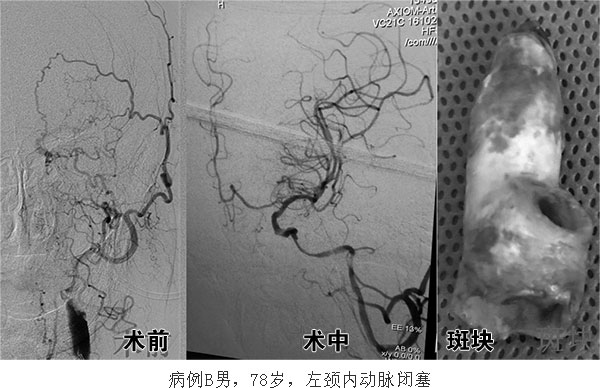

颈动脉狭窄的治疗方式有颈动脉内膜剥脱和血管内支架治疗两种。但当颈动脉完全闭塞后,其治疗难度大增,单纯介入开通,对斑块较硬的患者常难以成功,并且很难防止夹层、血栓脱落等并发症的发生。对慢性颈动脉闭塞,且具有缺血表现的患者,复合手术将成为他们的福音,通过颈动脉狭窄内膜剥脱手术切除颈内动脉起始部的斑块,在直视下将微导丝微导管放至远端颈内动脉的真腔中,再通过血管内球囊扩张或支架置入的方法开通已经闭塞的颈内动脉。